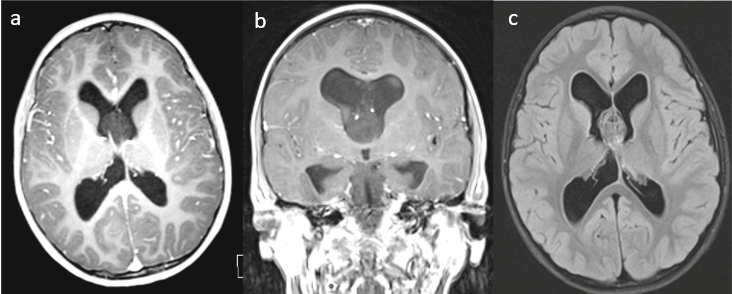

患者情况:7岁男孩,3周头痛病史,磁共振成像显示在透明隔中伴有脑积水的实质肿块

手术方法:通过电磁导航引导的右心室经皮层入路行肿瘤大部切除。由于肿瘤粘附于前突,因此不可能进行全切。

术后情况:手术后,没有新的神经系统疾病。术后既不使用放疗也不使用化学疗法。进一步的发展并不明显,并且该孩子在手术后2年的状态良好,没有神经系统症状。未出现头痛。定期的后续MR随访表明脑积水已经缓解,并且没有肿瘤复发的迹象。